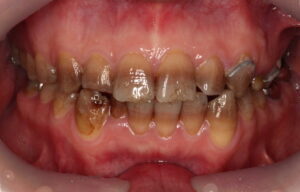

こちらはテトラサイクリン歯の1例です。

歯の1~2本だけでなく全体的な変色があるケースで審美的にマイナスになりがちです。

従来の方法では、ラミネートベニアやセラミッククラウンを行うために歯を削り、セラミック材料を被せて治す方法が主流でした。

今回は、削らないラミネートベニアでの治療についての症例写真となります。